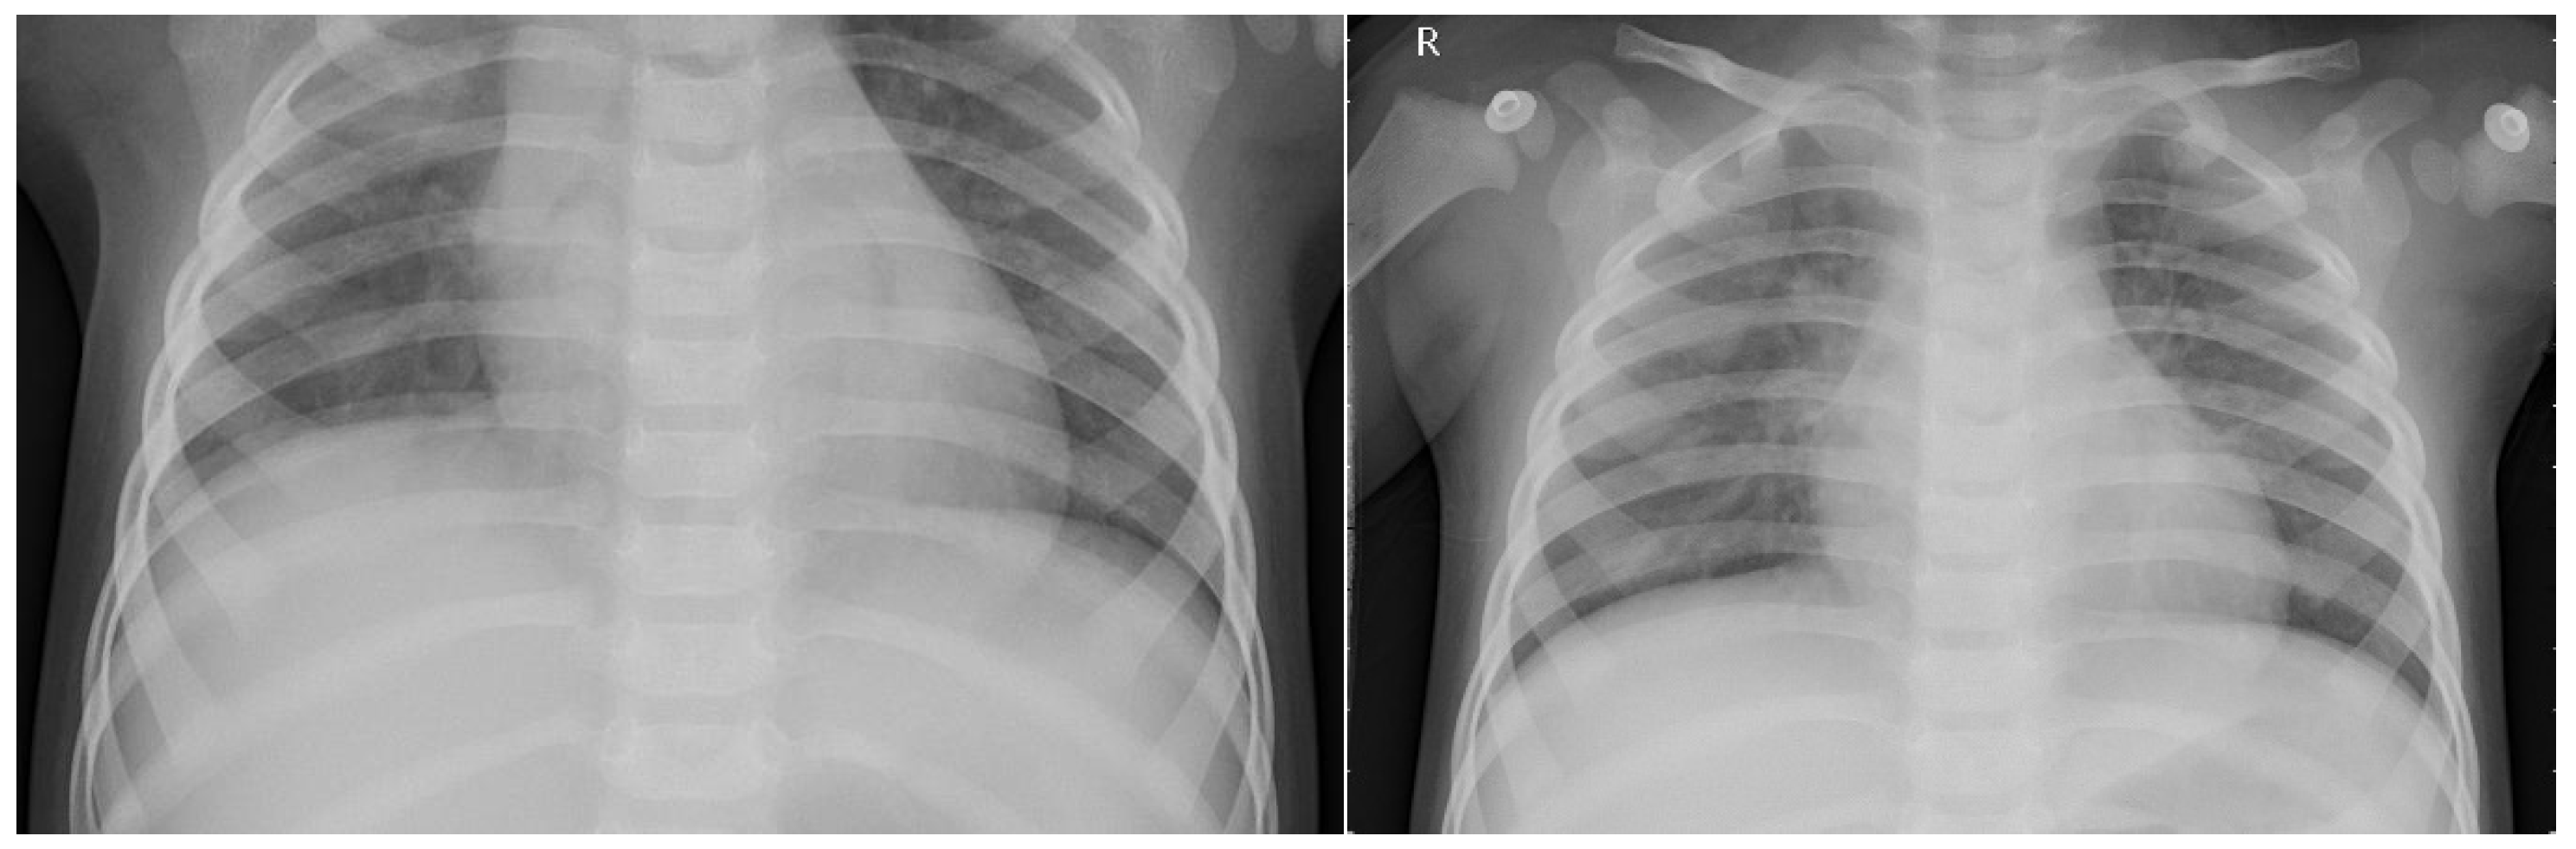

The original dataset used in this study was an open dataset—the Chest X-Ray dataset—obtained from Kaggle [25]. Originally, the dataset was composed of three folders (train, test, and val), where each folder consisted of two subfolders reflecting the two categories (NORMAL and PNEUMONIA). In total, there were 5863 grayscale JPEG images, with the train folder containing 5216 images (1314 NORMAL and 3875 PNEUMONIA), the test folder containing 624 images (234 NORMAL and 390 PNEUMONIA), and the val folder containing 16 images (8 NORMAL and 8 PNEUMONIA). Figure 5 shows two sample images (H × W or R × C = 2090 × 1858 and 1422 × 1152) from folder train\NORMAL, while Figure 6 shows two sample images (712 × 439 and 1240 × 840) from folder train\PNEUMONIA. For clarity of illustration, the pairs of images have been resized to the same height (4.92 cm for Figure 5; 4 cm for Figure 6).

Except for their different sizes, it is obvious from Figure 5 and Figure 6 that NORMAL images contain more peripheral parts than PNEUMONIA ones. Therefore, before applying these images, we need to understand the size differences among images in order to avoid wrongly interpreting the performance of the deep learning models, especially when the size difference may dominate during model training. Table 2 lists the statistics of sizes in the two categories, where R denotes the number of pixels by row, C for the number of pixels by column, and RC for the number of pixels by image, where mean and std. (standard deviation) are both rounded to the nearest whole number.

Based on the mean, it is obvious that NORMAL images are much larger than PNEUMONIA ones. According to experience, the distribution of image sizes can severely influence the classification results, potentially leading to biased judgments. As is well known, larger images will generally contain extra components, objects, or contents. When trained, deep learning models will learn these peripheral contents, not genuine information specific to pneumonia, therefore leading the models to make decisions according to these irrelevant features. Finally, deep learning models may obtain a higher accuracy under the same dataset, whereas the trained deep learning models will generally not be applied to other datasets due to a lack of generalization ability.

To obtain deep learning models with more generalization ability, the images of the original dataset need to be fairly pre-processed. Based on the center of each image, I cropped the original images to images of size 127 × 384—the smallest size in the dataset. All cropped images corresponding to the original images constituted the cropped dataset. In the following experiments, for the sake of conciseness and convenience, I refer to the cropped dataset as the original dataset (O) when there is no possibility of confusion. Figure 7 shows cropped images corresponding to those in Figure 5, and Figure 8 shows those corresponding to Figure 6.